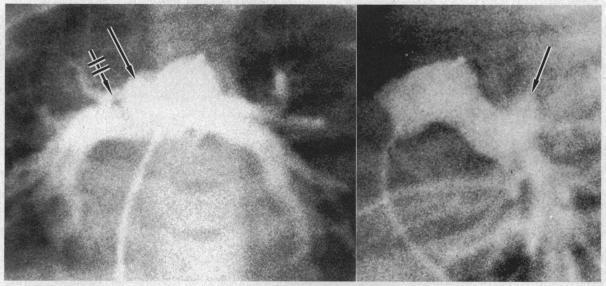

Partial tracheal obstruction due to anomalous origin of the left pulmonary artery.